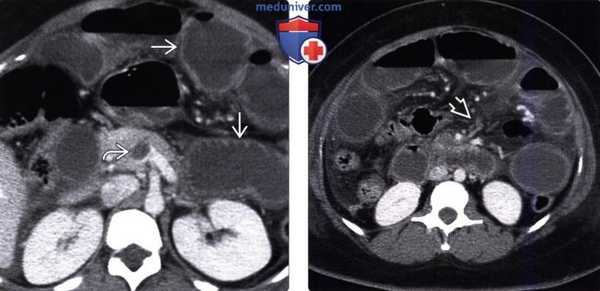

а,б - Пневматоз толстой кишки и газ в портальных венах у больного с ишемическим колитом. Пневматоз т кишки (а) проявляется изогнутым контуром газа (показано стрелками) по контуру заполненного жидкостью просве ходящей ободочной кишки.

На периферии левой доли печени (б) видно множество заполненных газом трубочек (пс стрелками). Компьютерная томография.

в - Симметричное утолщение (показано стрелкой) нижней части нисходящей ободочной кишки (едва заметное утолщение стенки) соответствует области, показанной белой стрелкой на рентгенограмме.

Компьютерная томография через верхнюю апертуру таза.

г - Ишемический колит у пациента с болевым синдромом в левом нижнем квадранте живота.

Обнаружено утолщение стенки нисходящей ободочной кишки (показано стрелкой) с расслоением в области стенки. Компьютерная томография.